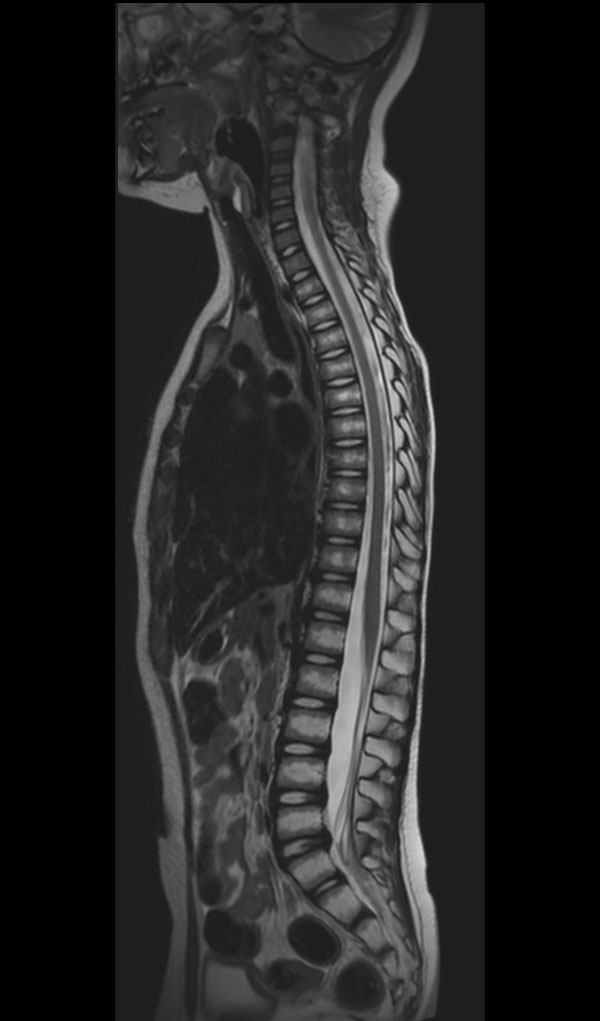

Premium Fat-free Pediatric Spine imaging

Phoenix Children Hospital, USA